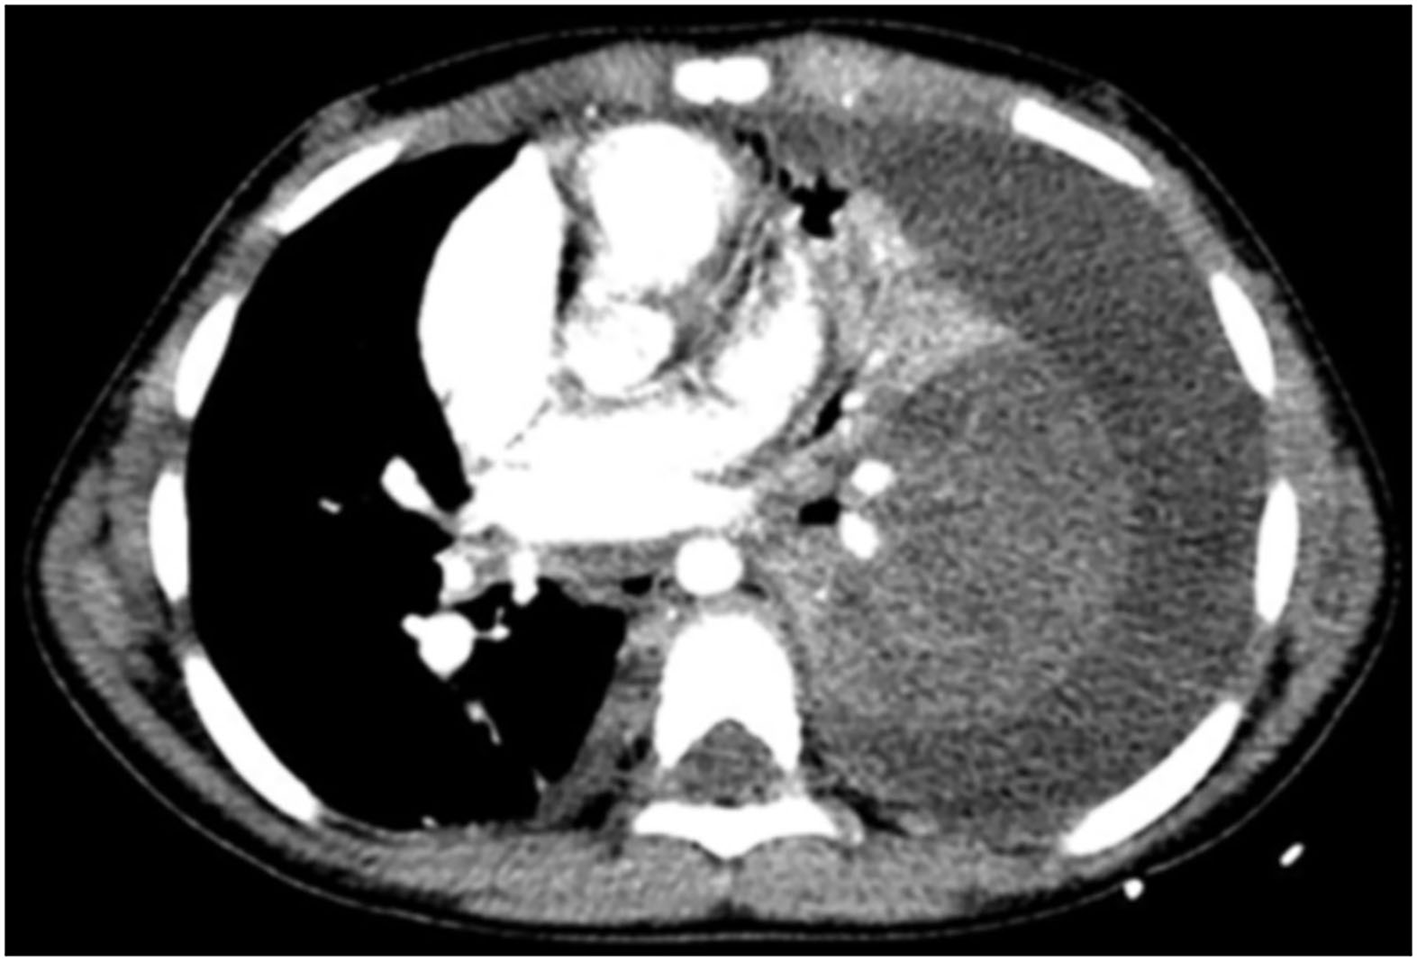

2. Lung parenchyma: forty-five cases (93.8%) presented unenhanced consolidation of the lung parenchyma after injection of a contrast agent. In 17 cases (35.4%), the necrosis was located in the left lower lobe (Figure 1); in 18 cases (37.5%), it involved the two lobes of the left lung; and in eight children (16.7%), the three lobes of the right lung. Cystic cavities were found in 38 cases (79.2%) and atelectasis of the necrosis lung in 42 cases (87.5%).

Figure 1

A 5-year-old patient with NP. Transverse slice of chest CT with injection in the mediastinum window shows heterogeneous enhancement of the parenchyma of the left lower lobe in keeping with NP before appearance of cavities. Also visible is a left pleural effusion causing partial atelectasis of the left lung.